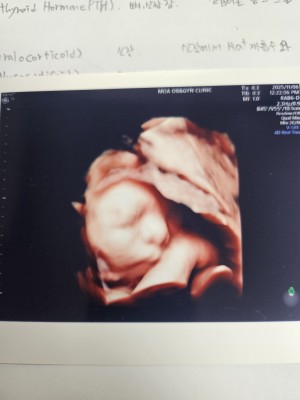

30주 입체초음파입니다 :)

이레IYRAE

2025-08-21

4

0